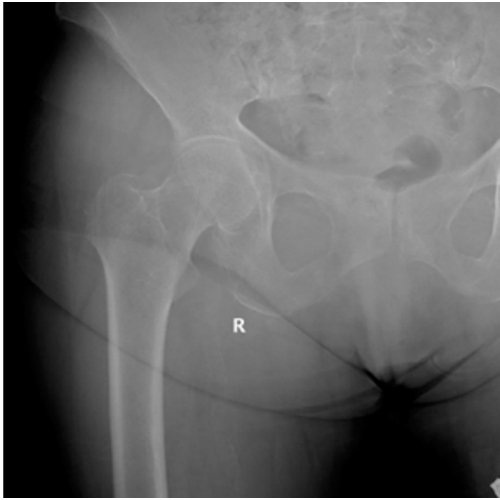

The patient had been evaluated one year earlier for a right inguinal pain of mechanical characteristics. Physical assessment was unspecific: range of motion was complete and pain free with no shortening of the right lower limb. Inguinal palpation was painless. Pelvic radiographs showed a stage I-II right coxarthrosis ((Tönnis classification) [8,9]. The patient was managed with pain killers. The patient was referred again for consultation due to lumbar pain with irradiation to the right inguinal region. She referred an insidious mechanical lumbar and inguinal pain during the last months. She did not report any traumatic event nor a trigger factor for that pain. The physical assessment showed lumbar pain, and rotations of the hip were painless. The hip X-ray at that stage showed no signs of femoral neck fracture (Figure 1). The lumbar spine X-rays were also normal. She was prescribed treatment with nonsteroidal anti-inflammatory drugs and physiotherapy for the lumbar region.

Figure 1: First visit right hip X- ray anteroposterior view. No signs of femoral neck fracture.